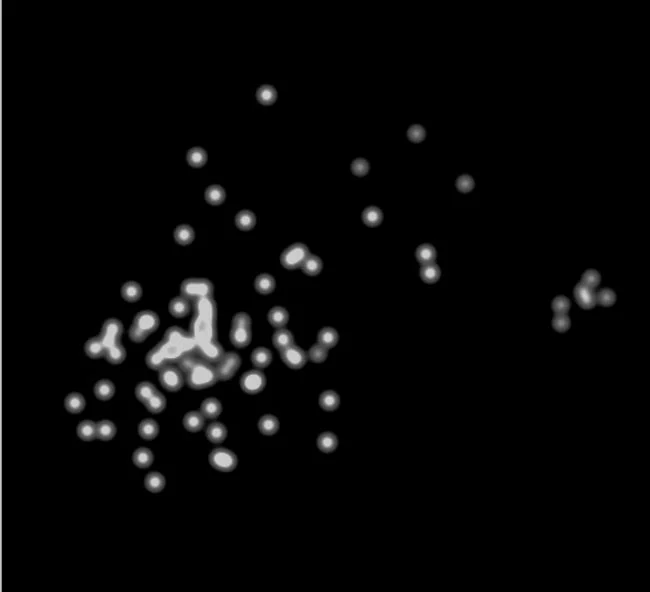

Liquid biopsy of abnormal brain barriers and dysfunctional neurovascular unit project

We are dissecting vascular contributions to brain degeneration down to cellular and molecular effects by using extracellular vesicles as a liquid biopsy approach. Cell-specific EV molecular quantifications represent a novel approach to biomarker quantification with greater cellular specificity. We are currently performing proteomics and other molecular omics quantifications from vascular cell-derived EVs for discovery of VCID-associated molecular signatures. In parallel we are working on improving the ease of cell-specific EV isolation, with emphasis on technical reliability. Here our goal is to turn discoveries into reliable biomarkers by developing isolation approaches that do not require technical expertise and can be used by all.